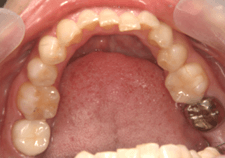

症例.5 健康な歯を引っ張り出す

| 虫歯で歯が少ない状態です。 歯と歯茎の境目が不明瞭です。 |